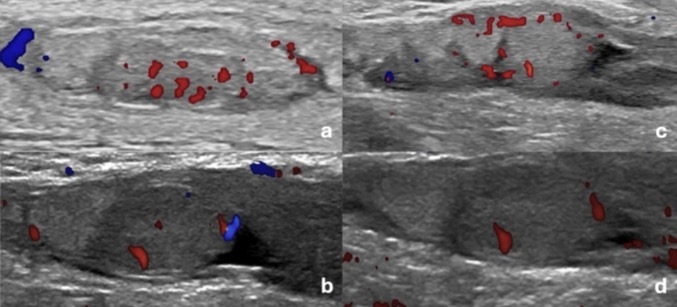

A J3: a,b: Testicule Dt c,d: Testicule gauche